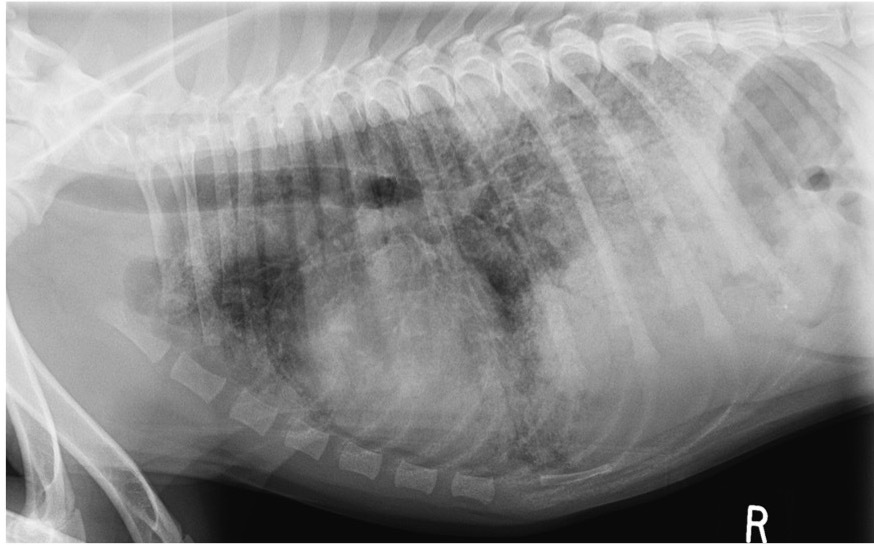

Which lung pattern is shown here?

Alveolar pattern

This pattern creates a soft tissue-like opacity within the lungs; think of it as heavy fog obscuring structures.

There is border obliteration (we can no longer clearly distinguish the cardiac silhouette).

We can still see air bronchograms because alveolar diseases spared the airways.